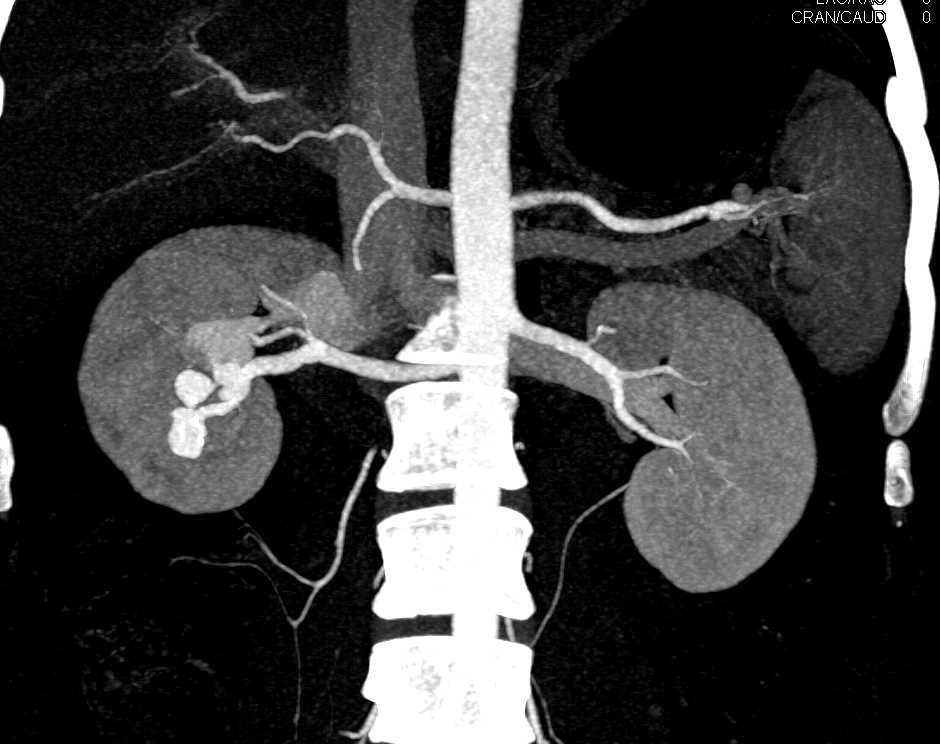

Lymphomatous Infiltration of the Kidneys